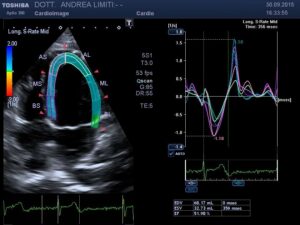

L’ecocardiografia è una metodica nella quale gli ultrasuoni sono utilizzati per visualizzare l’interno del cuore ed il flusso del sangue attraverso le valvole. A differenza delle radiazioni utilizzate in radiologia, gli ultrasuoni sono innocui, per cui non è necessaria alcuna precauzione e l’esame può essere eseguito su qualunque paziente innumerevoli volte (anche nelle donne in gravidanza).

Durante l’esame la sonda viene appoggiata al torace del paziente e gli ultrasuoni vengono diretti all’interno del corpo, senza che il paziente possa avvertirli. Gli ultrasuoni arrivano al cuore e ritornano alla sonda generando echi che sono utilizzati per visualizzare sullo schermo un cuore “virtuale” che ci informa del comportamento del cuore reale del paziente. Le onde sonore possono essere riflesse anche dal sangue in movimento all’interno del cuore e fornire informazioni sul flusso all’interno del cuore e dei vasi.

Questo fenomeno è chiamato Doppler.

Durante un esame Doppler il paziente sente un rumore prodotto dalla macchina che rappresenta il flusso del sangue attraverso le valvole del cuore. Le informazioni che si rilevano con questo esame sono diverse e complementari a quelle che si acquisiscono con l’elettrocardiogramma.